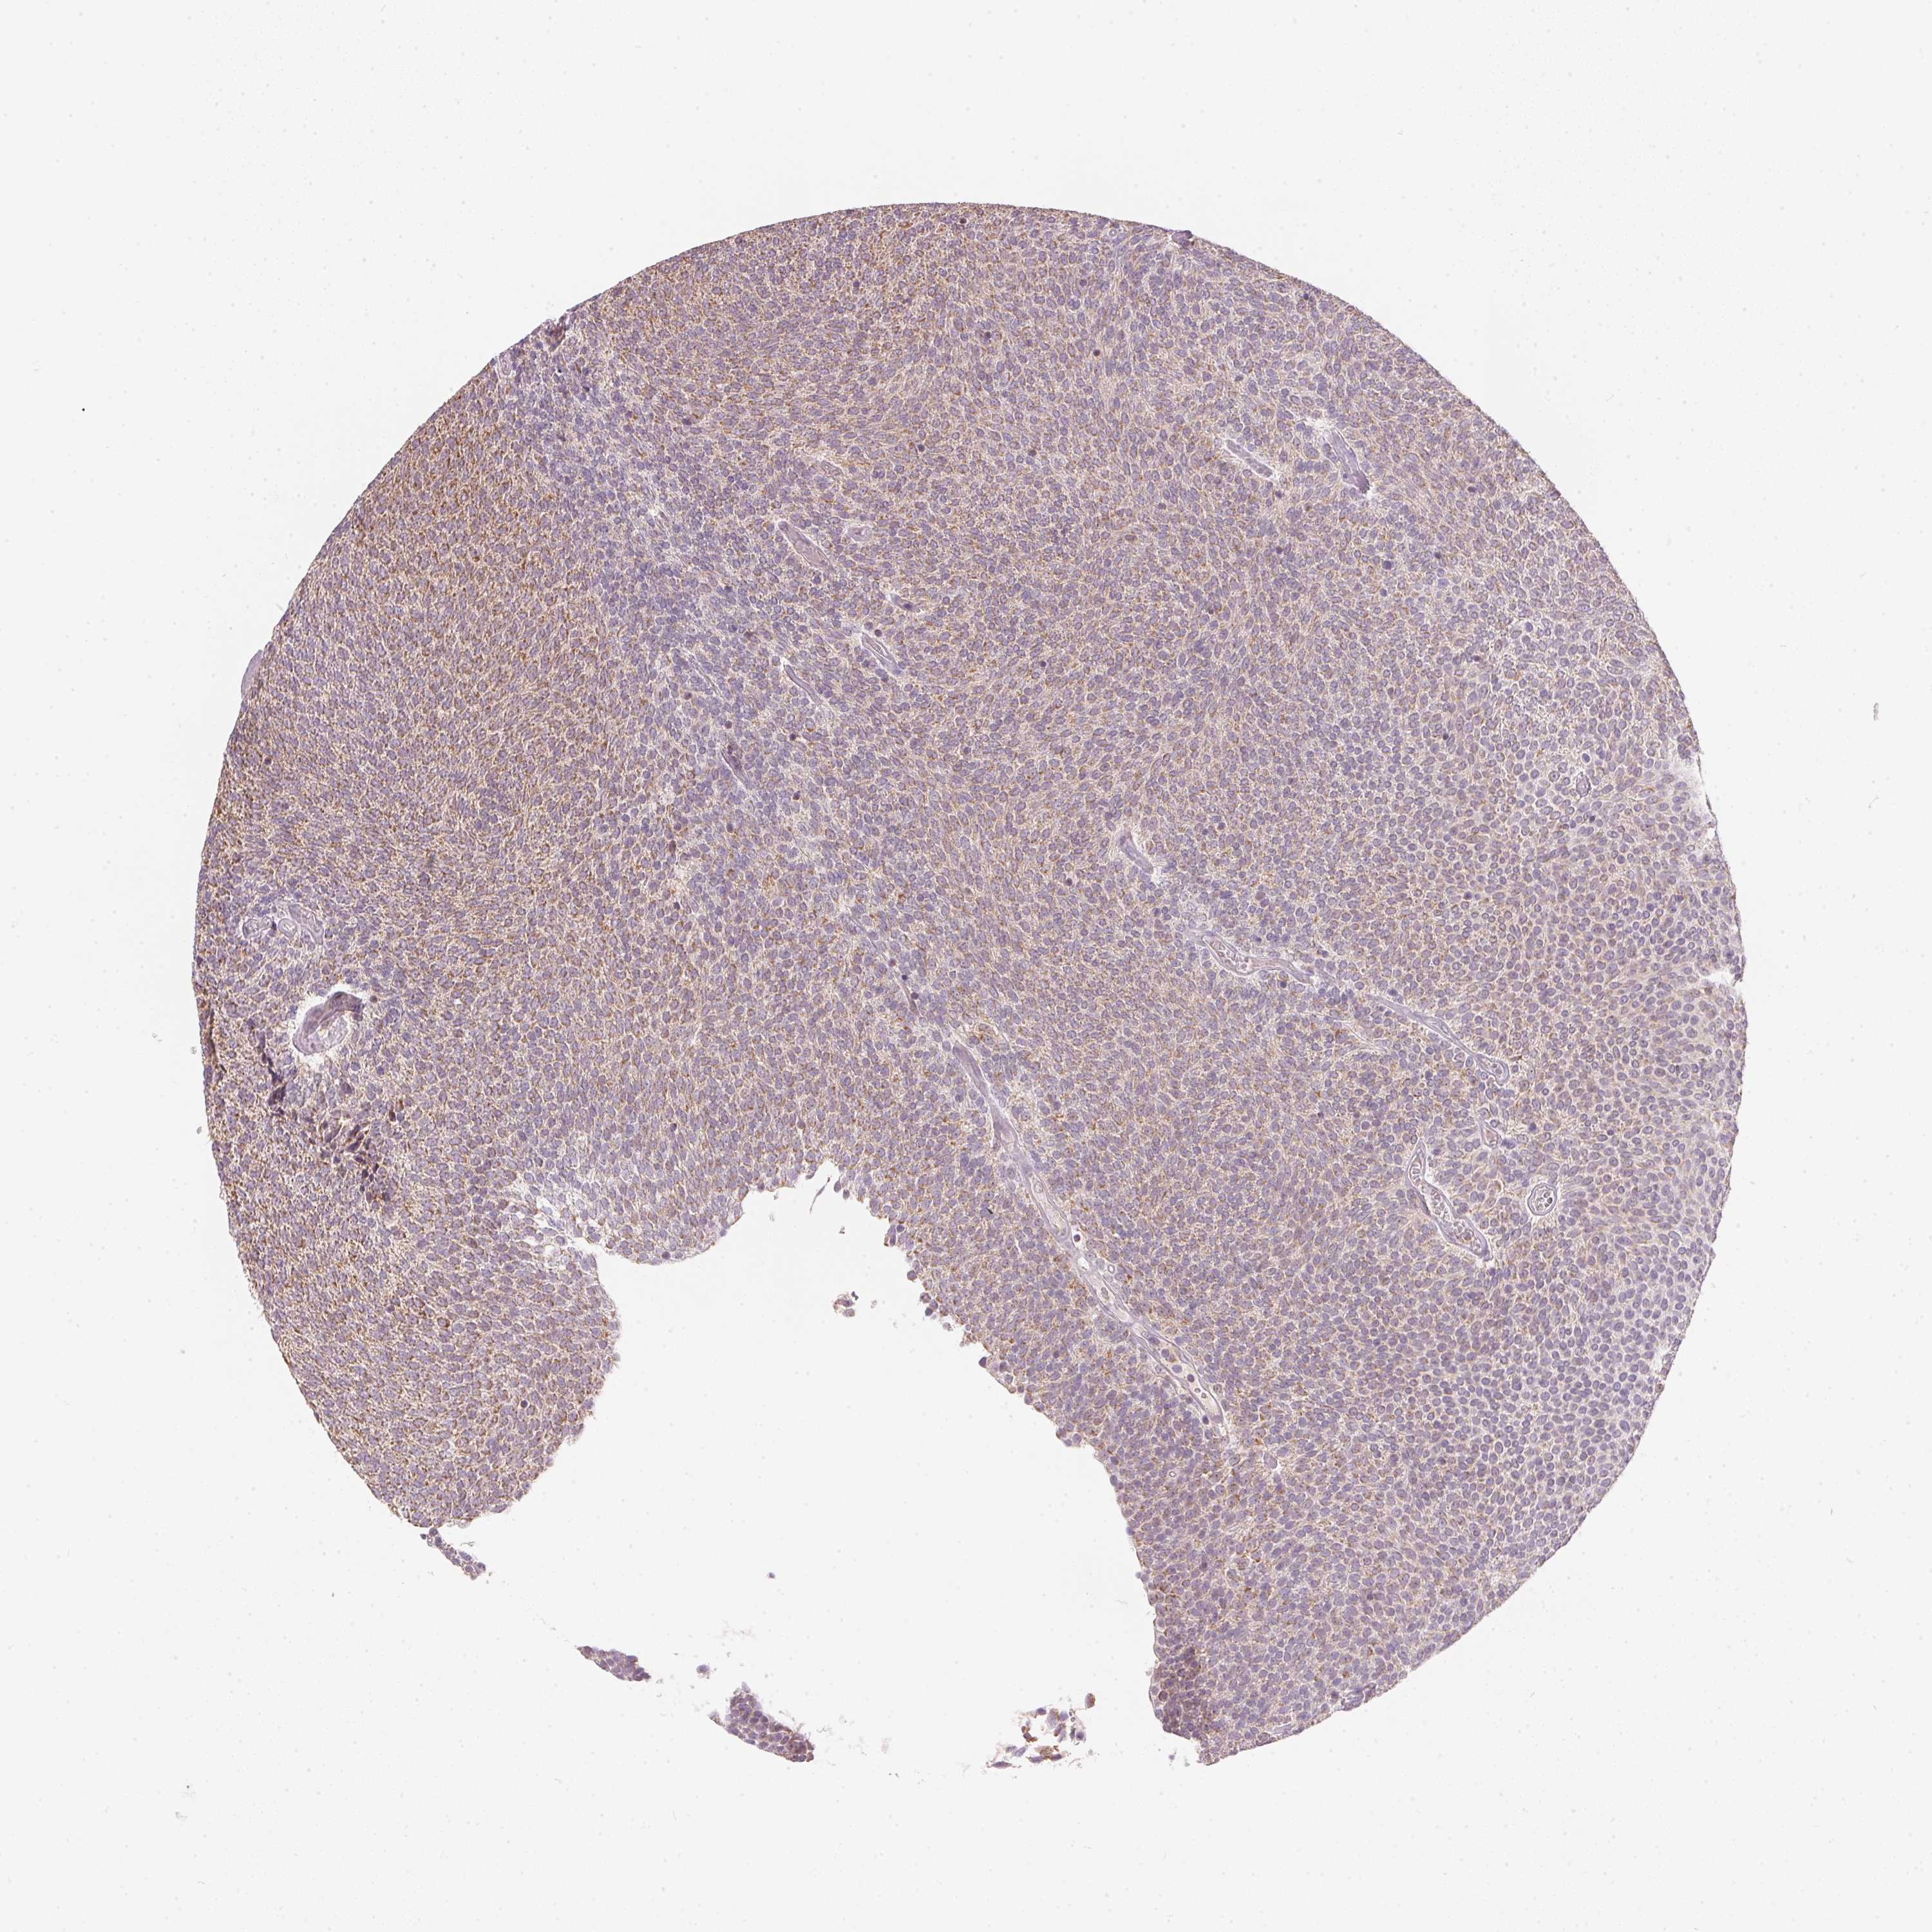

UROTHELIAL CANCER - Protein expressioni

A mouse-over function shows sample information and annotation data. Click on an image to view it in a full screen mode. Samples can be filtered based on level of antibody staining by selecting one or several of the following categories: high, medium, low and not detected. The assay and annotation is described here.

Antibody stainingi

Antibody staining in the annotated cell types in the current human tissue is reported as not detected, low, medium, or high, based on conventional immunohistochemistry profiling in selected tissues. This score is based on the combination of the staining intensity and fraction of stained cells.

Each image is clickable and will lead to virtual microscopy that enables deeper exploration of all samples and also displays staining intensity scores, fraction scores and subcellular localization as well as patient and tissue information for each sample.

Antibody HPA067252

Staining

High

Medium

Low

Not detected

Intensity

Strong

Moderate

Weak

Negative

Quantity

>75%

75%-25%

<25%

None

Location

Nuclear

Cytoplasmic/membranous

Cytoplasmic/membranous,nuclear

Urothelial carcinoma, High grade

Urothelial carcinoma, NOS

Urothelial carcinoma, Low grade